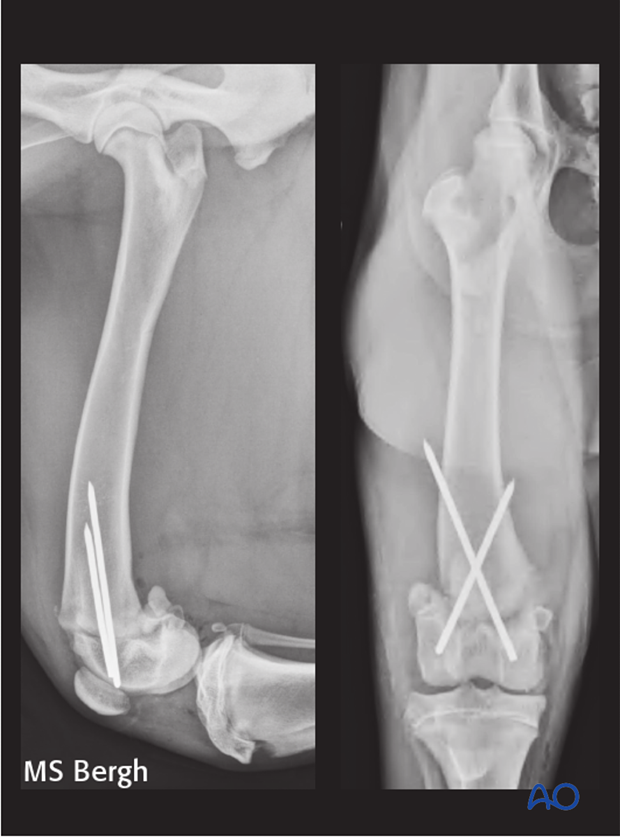

Radiographs show malreduction of the distal physeal fracture resulting in a rotational malalignment and under-reduction of the distal fragment. Note the femoral head anteversion.